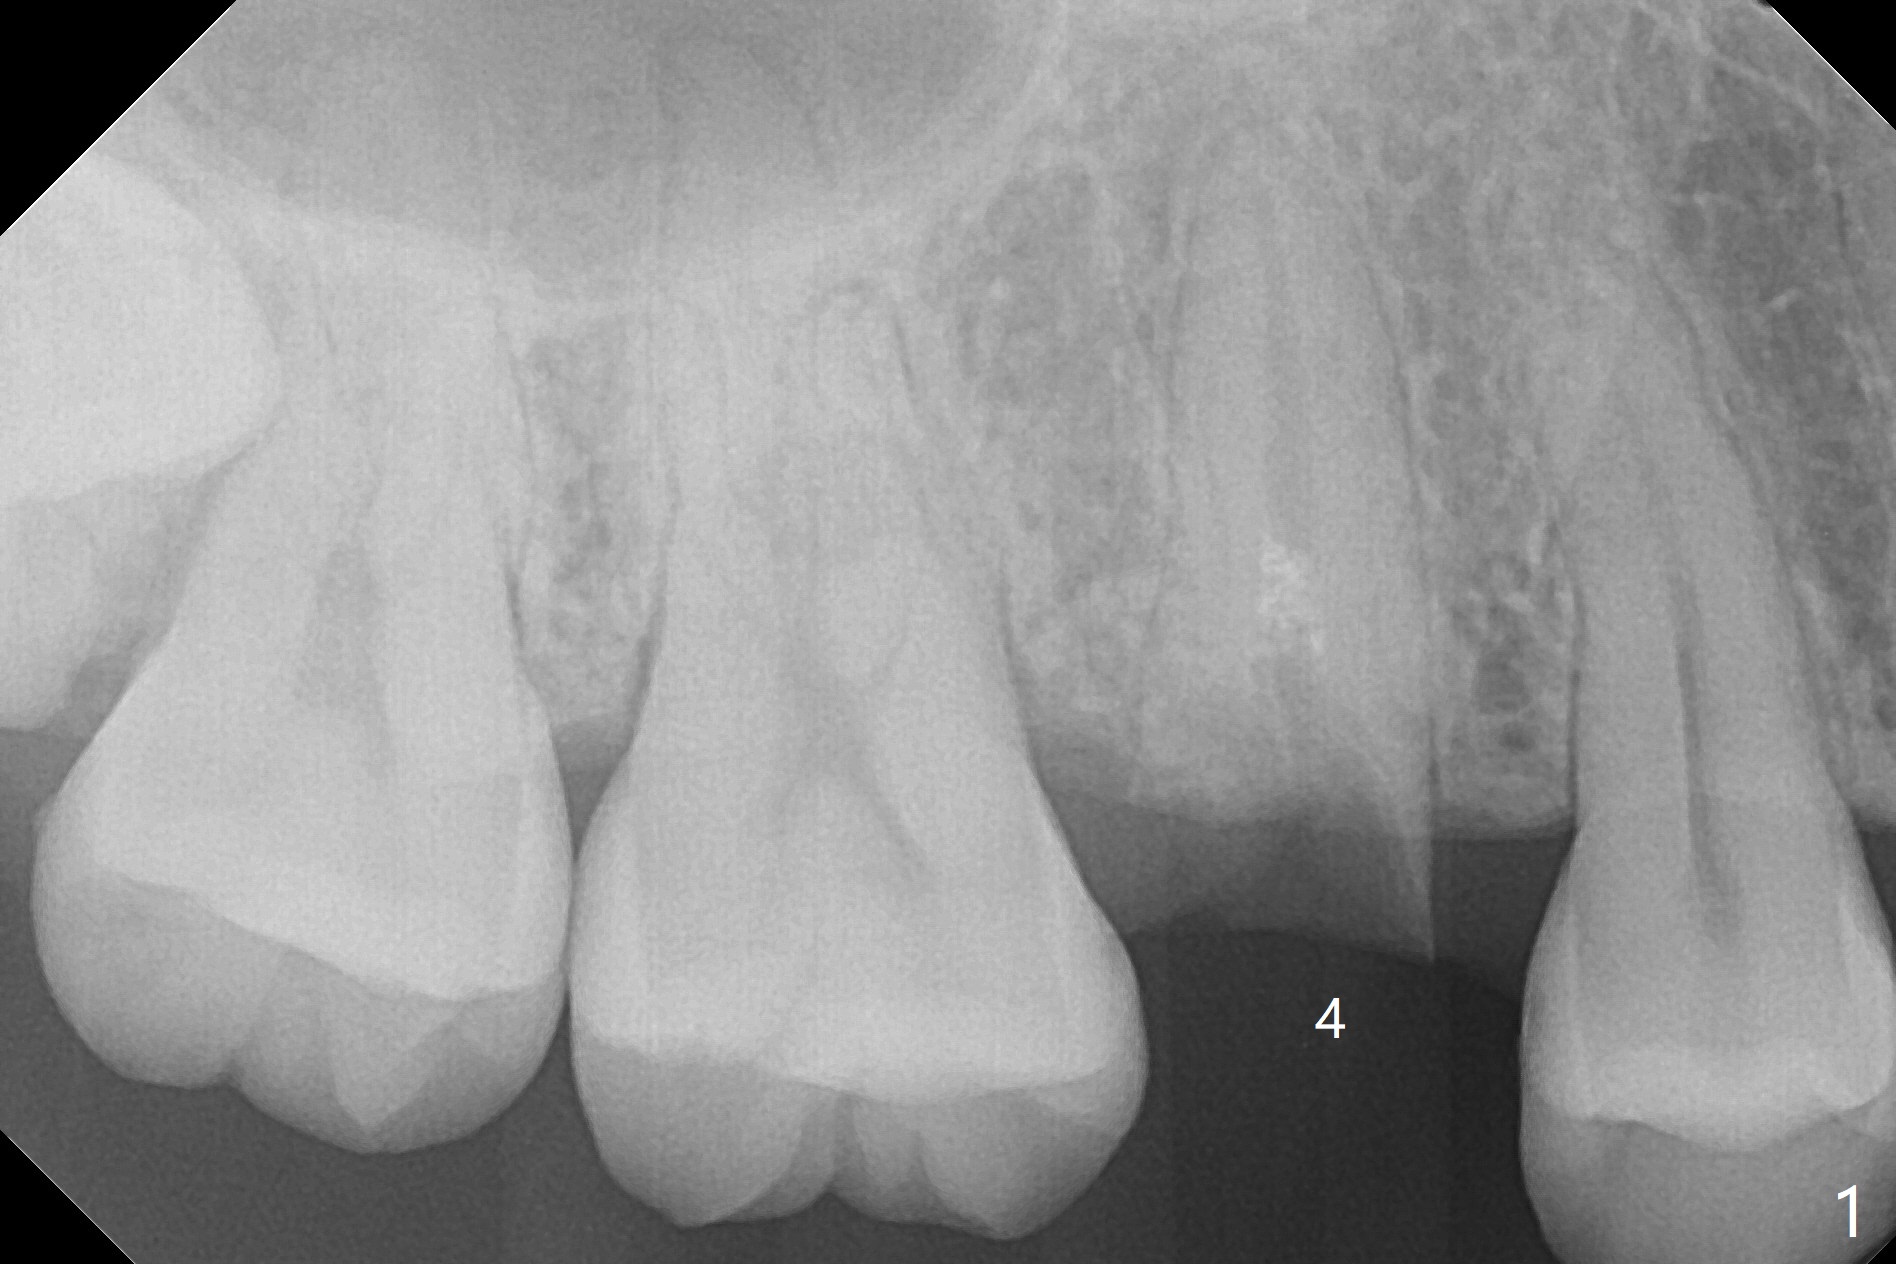

A 29-year-old woman requests implant for the residual root of the tooth #4 after initial RCT in home country (Fig.1,2 (S: sinus)). It appears that a 15 or 16 mm long implant should be placed to engage into the apical native bone and sinus floor (*) for stability (Fig.3,4). Further stability is obtained by contact with the mesial (M), distal (D) wall or both.